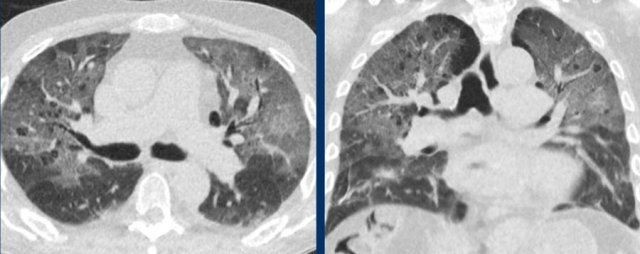

Influenza pneumonia

Viral pneumonias show overlapping features on CT.

Influenza virus infection can result in bilateral ground-glass opacities, consolidations and crazy paving that appear similar to COVID-19.

Typical features of influenza are:

- Mucoid airway impaction

- Linear opacities

- Central distribution (as shown in these two cases)

In addition, vessel thickening and upper lobe involvement seem to occur more frequently in the abnormal COVID-19 parenchyma than in other viral pneumonias.